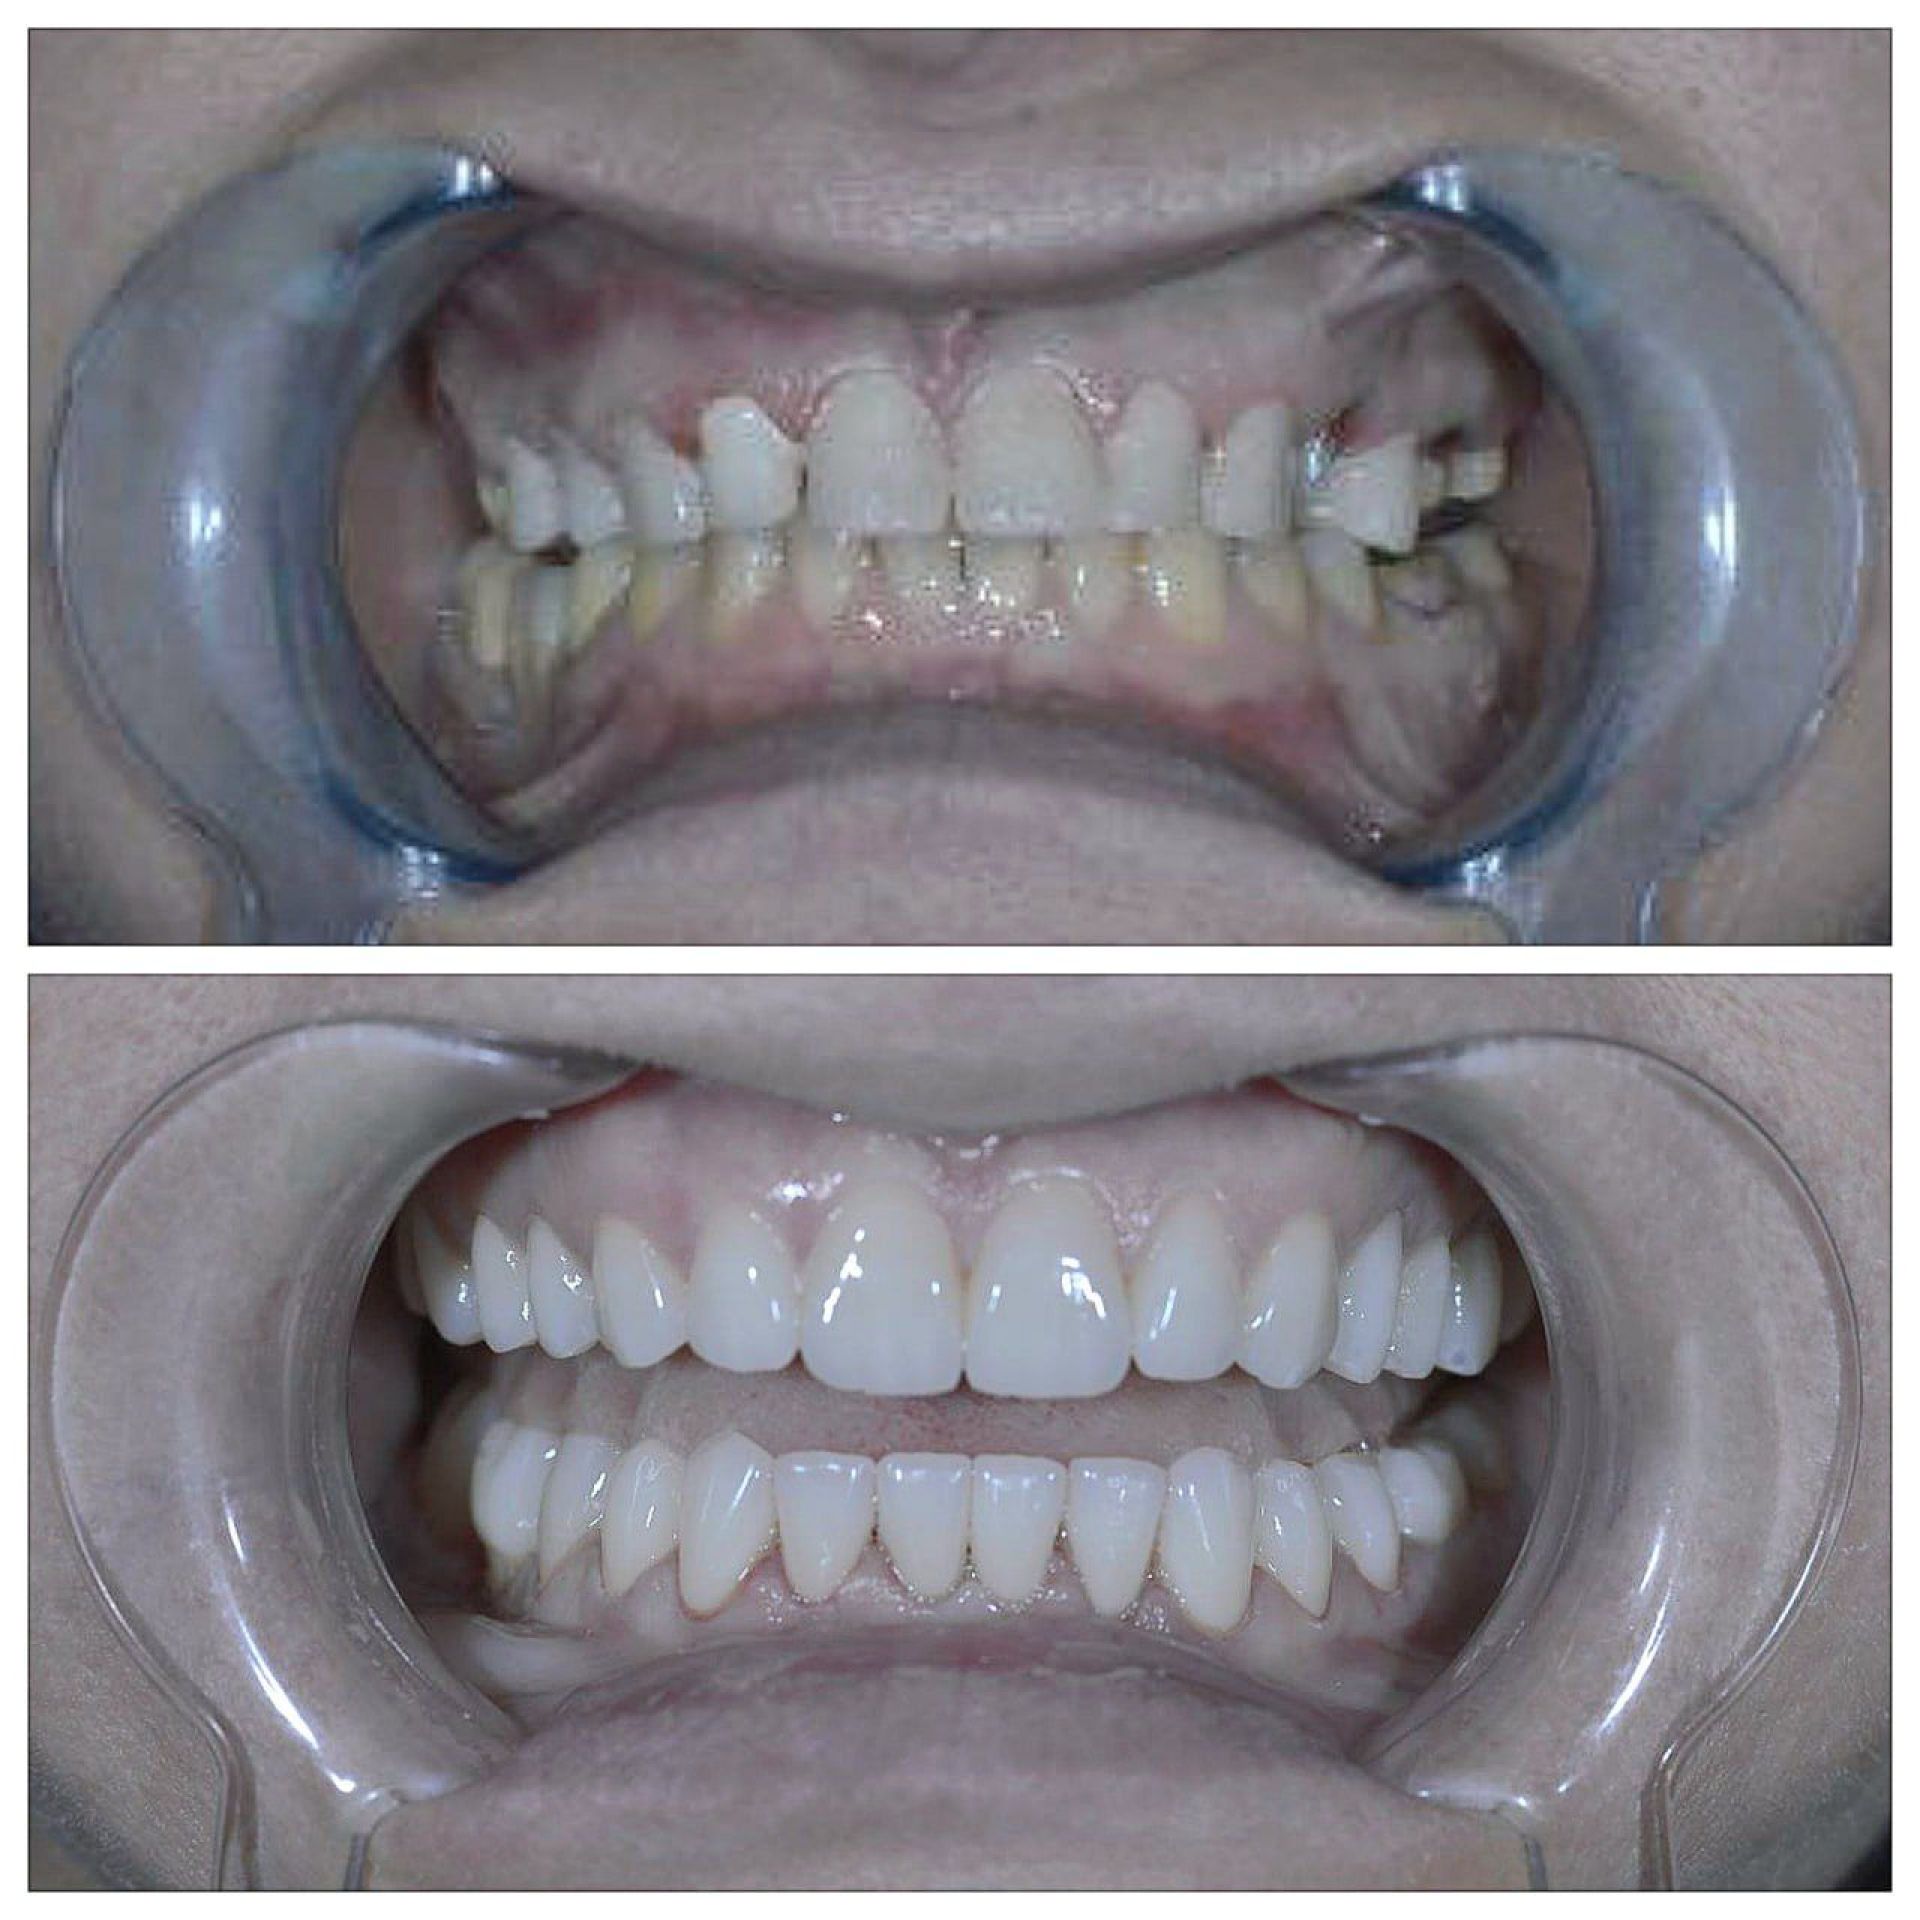

«Стоматологія Олексюка» пропонує високоякісні послуги в галузі імплантації зубів, яка здатна кардинально покращити ваше життя. Завдяки сучасним методам імплантація дозволяє легко та безтурботно відновити втрачені зуби, забезпечуючи Вам впевненість у собі.

Імплантація полягає у встановленні штучного зубного кореня та відновленні коронки за допомогою ортопедичної конструкції. Операція виконується під анестезією, що робить її абсолютно безболісною. Процес відновлення після операції відбувається швидко, що дозволяє вам швидко повернутися до звичайного життя.

Однією із переваг, які пропонує «Стоматологія Олексюка», є негайна імплантація. Цей метод дозволяє встановити імплантат безпосередньо після видалення пошкодженого зуба. Такий підхід гарантує високу точність і швидке відновлення, оскільки кістка ще не зазнала деформацій.

Пацієнти, які обирають негайну імплантацію, отримують такі переваги:

- Швидке повернення до повноцінного життя.

- Менш травматичний та більш ефективний процес.

- Мінімальна кількість візитів до стоматолога.